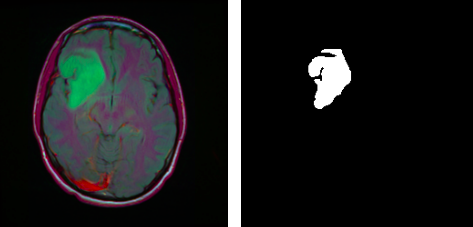

To create segmentation masks for tumors in the human brain using MRI scans.

Sample images for trying out model Inference Images